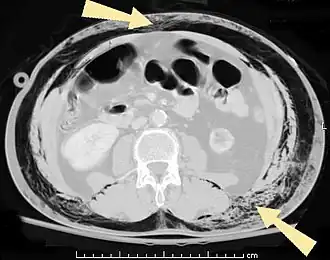

![]() КТ брюшной полости пациента с подкожной эмфиземой (указано стрелками) | |

В результате анатомической особенности клетчатки — отсутствия фасций — воздух довольно быстро распространяется на грудную клетку, шею, лицо, а также вниз на живот до мошонки (у мужчин) и бёдер[2].